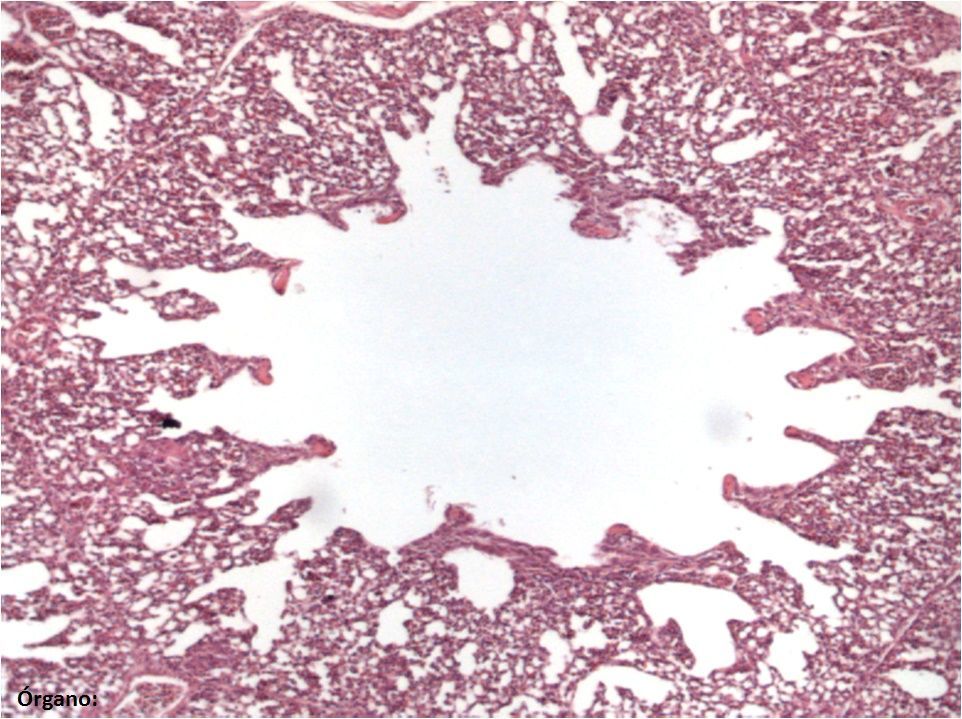

Question

Escriba el nombre de las estructuras marcadas (una sola palabra por cada estructura) y del órgano (abajo a la izquierda) especificando si es de ave o mamífero (ej. molleja de ave). Nota: tenga en cuenta los acentos y las faltas de ortografía.

Answer

• Parabronquio

• Atrio

• Infundíbulo

• Pulmón de ave